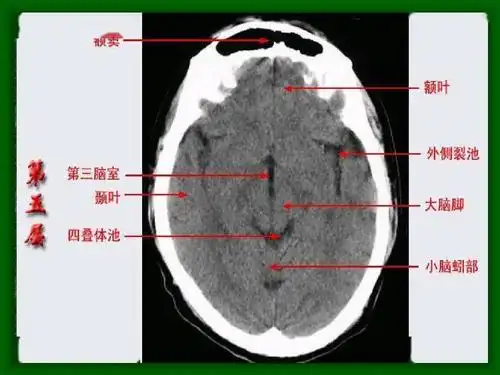

头颅ct 解剖图谱,人手一份